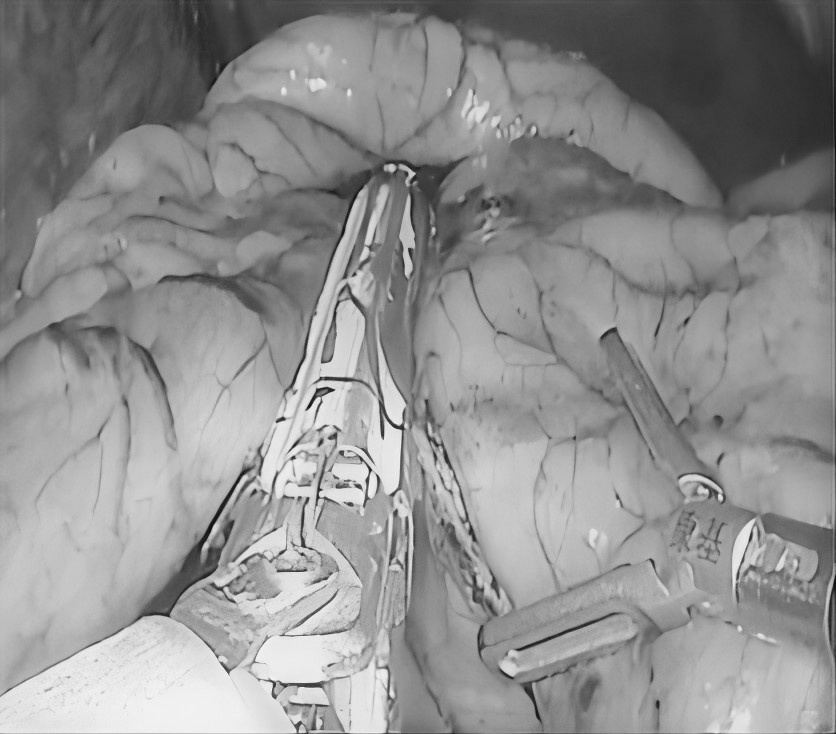

近日,贵州航天医院普外科特邀贵州医科大学附属医院胃肠外科严芝强博士前来我院开展“腹腔结核的综合治疗”学术讲座,严博士结合临床实际案例,带来了腹腔结核综合治疗的前沿知识和宝贵经验,深入浅出地讲解了腹腔结核的发病机制、诊断要点、最新治疗策略及药物精准治疗、把握手术干预时机、营养支持等关键环节,为提升我院腹腔结核诊治水平奠定了坚实基础。 今天,小编就带领大家回顾讲座内容,你想要了解“腹腔结核”知识都在这里! 什么是腹腔结核? 结核病是由结核分枝杆菌引起的传染病,曾是单一传染源死亡的主要原因,能影响身体多个器官,腹腔结核就是其中之一,包括胃肠道、腹膜、肠系膜淋巴结等部位的结核病。 腹腔结核常见症状 消化系统症状:常见为腹痛,可能伴有呕吐、腹胀、恶心、腹泻或便秘等症状。如:频繁呕吐,无法正常进食;长期受腹胀困扰,腹部隆起。 全身症状:发热、盗汗、体重减轻等。如:不明原因地体重下降,身体逐渐消瘦,夜间睡觉时大量出汗。 腹腔结核发病原因 消化道感染:食(饮)用带菌牛奶或被结核菌污染食物,进入消化道后,结核菌在肠道淋巴组织中形成病灶,并可能蔓延至肠系膜淋巴结、腹膜等部位。如,经常喝未经严格消毒的牛奶,增加感染风险。 血行播散:身体其他部位的结核菌,通过血液循环到达腹腔,侵犯腹腔内器官。如肺结核,当患者免疫力下降时,结核菌就可能“乘虚而入”进入血液,进而播散到腹腔。 淋巴结播散:胸腔内淋巴结结核或全身粟粒型结核,结核菌可通过淋巴管道传播至腹腔淋巴结,引发腹腔结核。 腹腔结核治疗方式 1.早期、联合、全程规范化抗结核治疗(治疗原则)。 2.加强支持治疗。 3.抗结核化学药物治疗:一般三联或四联。 4.放腹水,可同时腹腔内注射药物治疗。 5.手术治疗:仅限于完全性肠梗阻、肠瘘或并发肠穿孔者,当本病诊断有困难,与腹内肿瘤或某些急腹症不能鉴别时,可考虑剖腹探查。 腹腔结核饮食注意 腹腔结核患者饮食少量多餐,控制高脂、肥腻食物摄入,多吃清淡、易消化的食物,适量补充高蛋白等营养,多吃富含纤维素的新鲜蔬菜和水果,促进肠腔及腔腹部蠕动,禁食辛辣刺激性食物,忌烟酒。 腹腔结核预防建议 如果感染腹腔结核,一定要到正规医院做正规抗结核治疗,积极配合,树立战胜疾病的信心,就能战胜病魔,恢复健康。 近年来,腹腔结核发病率呈上升趋势,因其诊疗复杂、病情多变,常累及肠道、腹膜等多脏器,致患者腹痛、肠梗阻,严重影响生活质量,甚至危及生命。 对此,贵州航天医院普外科依托结核内科结核病诊疗经验,积极开展腹腔结核外科治疗工作,通过内外科联合,着力打造腹腔结核诊疗体系,为遵义地区腹腔结核患者提供更加优质、全面的诊疗服务。 咨询信息:贵州航天医院便民服务电话(请点击跳转咨询电话页面) 注:部分图片来源于网络,如有侵权,请联系删除。 贵州航天医院普外科专家团队 梁 跃 普外科主任 主任医师 临床擅长:对普外科各类肿瘤手术具有丰富的临床经验。 毕业于遵义医学院,遵义市医学会小儿外科学分会常务委员,遵义市肛肠协会理事,遵义市医学会核医学分会(第二届)委员会委员;荣获第三期“黔医人才计划”优秀学员称号;主持市级课题1项,完成省级课题1项,在国内各类刊物上发表论文10余篇。 钱科洪 普外科 副主任医师 临床擅长:从事普外科临床工作30余年,对各类普外科疾病的诊治、乳腺、甲状腺、胃十二指肠、结直肠等疾病及疑难杂症具有丰富的临床诊疗经验。 毕业于遵义医学院临床医疗系,2009年前往中山大学附属第一医院微创外科进修学习,在国内各专业期刊发表论文数篇。 贵州航天医院普外科简介 基本情况 贵州航天医院普外科成立于1968年,前身属于航天部O61基地3417医院外一科,1998年3417医院、3427医院合并后更名为普外科,下设胃肠外科、肛肠外科2个亚专业科室,拥有在全市较为先进的专科设备和技术,是中国疝病专科联盟单位,贵州医科大学附属医院胃肠外科专科联盟单位。开放床位40张,配备医护人员21人。 专科特色 普外科致力于胃肠及肛肠疾病的外科临床诊治及科研,以腹腔镜微创外科技术为本,形成以快速康复治疗胃肿瘤、结直肠肿瘤、小肠肿瘤、直肠脱垂、肥胖病、急腹症、各类疝、痔、瘘等专科特色,同时注重胃肠疾病尤其是结直肠恶性肿瘤的基础研究和临床转化研究,总体诊断和治疗水平在区域同级医院居于领先水平。 开展手术:腹腔镜下胃癌根治术,腹腔镜下袖状胃切除术,腹腔镜下胃肠道间质瘤切除术,腹腔镜下结、直肠癌根治术,胃癌、结直肠癌的精准治疗,腹腔镜下小儿疝气、成人疝修补术,腹腔镜下阑尾手术,内痔的硬化注射治疗及痔疮的微创治疗:ATH、PPH、TST,直肠脱垂的各种手术治疗,难治性伤口VSD技术,鼻胃肠管、肠梗阻导管置入术,肛肠术后间歇性导尿技术,并引进了中医适宜技术,也为各种化疗患者提供输液港安装,提高患者就医体验。 腹腔镜下腹股沟疝无张力修补术 腹腔镜下腹股沟疝 无张力修补术 腹股沟疝里金斯坦(Lichtenstein)手术 PPH微创术治疗环状混合痔 黏连性或炎性肠梗阻-肠梗阻导管 腹腔镜袖状胃切除 腹腔镜阑尾切除术 腹腔镜阑尾肿瘤切除术 腹腔镜下结肠癌根治术 诊疗范围 胃肿瘤、结直肠肿瘤、小肠肿瘤、肥胖症、各类急腹症、腹部外伤、腹壁疝、便秘、直肠脱垂、痔疮、肛瘘、肛裂等胃肠、肛肠外科疾病。 END